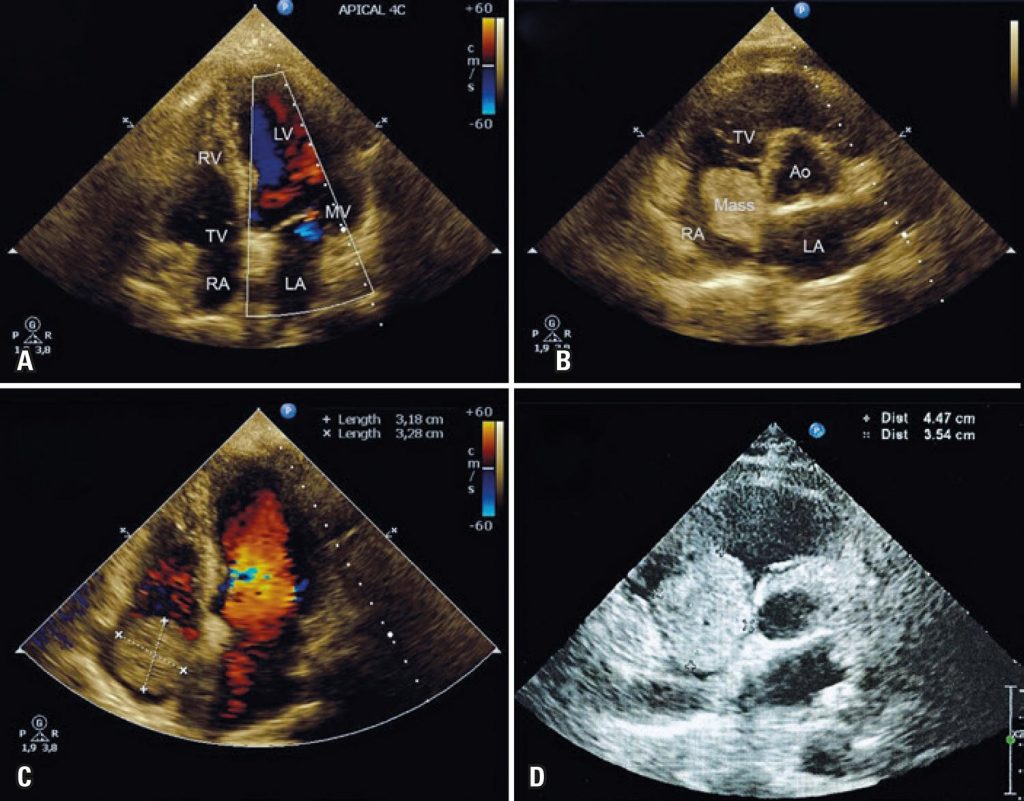

Fast growth rate of a right atrial myxoma

Primary cardiac tumors are rare, with an incidence between 0.0017 and 0.19%, and are asymptomatic in up to 72% of cases. Approximately 75% of tumors are benign, and nearly 50% of these are myxomas. Concerning location, 75% of myxomas are in the left atrium, 15 to 20% in the right atrium, and more rarely in the ventricles. The finding of cardiac myxomas usually implies immediate surgical excision to prevent embolic events and sudden cardiac death. Reports with documented growth rate are rare, and the actual growth rate remains a controversial issue. We report the rapid growth rate of a right atrial myxoma in an oligosymptomatic 69-year-old patient, with negative previous echocardiographic history in the last two years, who refused surgery upon diagnosis, enabling monitoring of myxoma growth.